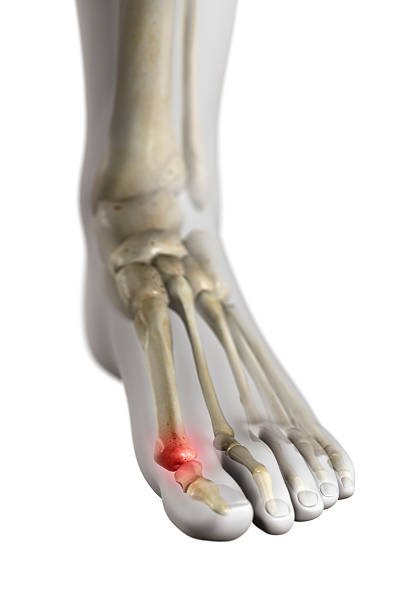

종자골염은 엄지발가락 아래쪽에 위치한 작은 뼈인 종자골(sesamoid bone)에 염증이나 통증이 발생하는 질환으로, 주로 반복적인 압력이나 충격으로 인해 발생합니다. 이 부위는 체중이 집중되는 부위 중 하나로, 보행이나 운동 시 지속적으로 자극을 받기 쉬우며, 특히 하이힐을 자주 신거나 달리기, 점프 등의 활동을 자주 하는 사람에게 잘 나타납니다. 종자골염은 초기에는 가벼운 통증으로 시작되지만, 시간이 지남에 따라 발바닥 앞쪽의 통증이 심해지고, 걸을 때 불편함을 초래하거나 발을 디딜 때 찌릿한 통증이 느껴지는 등 일상생활에 큰 영향을 미칠 수 있습니다. 본 글에서는 종자골염의 주요 원인 10가지를 중심으로, 나타나는 증상과 진단 방법, 그리고 효과적인 치료법과 재발 방지를 위한 관리법에 대해 구체적으로 살펴보겠습니다.

종자골염의 대표적인 증상은 발 앞쪽, 특히 엄지발가락 아래 부위의 통증입니다. 이 통증은 서 있거나 걷거나 뛸 때 더욱 심해지며, 장시간 활동 후에는 발바닥이 욱신거리거나 짓눌리는 느낌이 들 수 있습니다. 일부 환자는 국소적인 부기나 압통, 열감을 느끼기도 하며, 통증으로 인해 발을 절거나 무의식적으로 보행 자세가 바뀌는 경우도 있습니다. 증상이 심해지면 신발 신는 것조차 불편해지고, 심한 경우 발을 디디기 어려운 상태에 이를 수 있습니다. 특히 뻣뻣한 바닥을 맨발로 걸을 때 통증이 뚜렷해지며, 뼈를 누를 때 날카로운 통증이 느껴질 수 있습니다. 종자골염은 만성적으로 진행되는 경우가 많아 조기에 적절한 관리가 이루어지지 않으면 지속적인 통증과 활동 제한이 동반되며, 이로 인해 일상생활의 불편과 삶의 질 저하로 이어질 수 있습니다. 따라서 초기 증상을 인지하고 빠르게 대처하는 것이 매우 중요합니다.